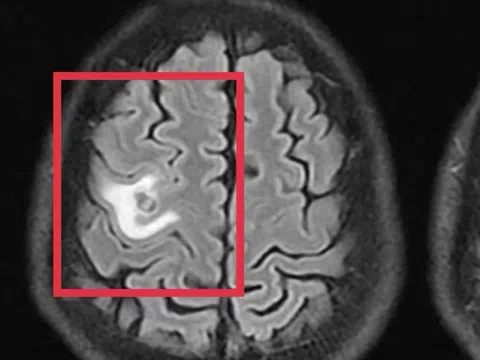

Kinh dị sán dây chó làm tổ trong não người đàn ông, gây tê tay, co giật

12:00 24/12/2025

Nam bệnh nhân nhập viện trong tình trạng co giật, đau đầu, những biểu hiện dễ khiến nhiều người nghĩ đến u não.